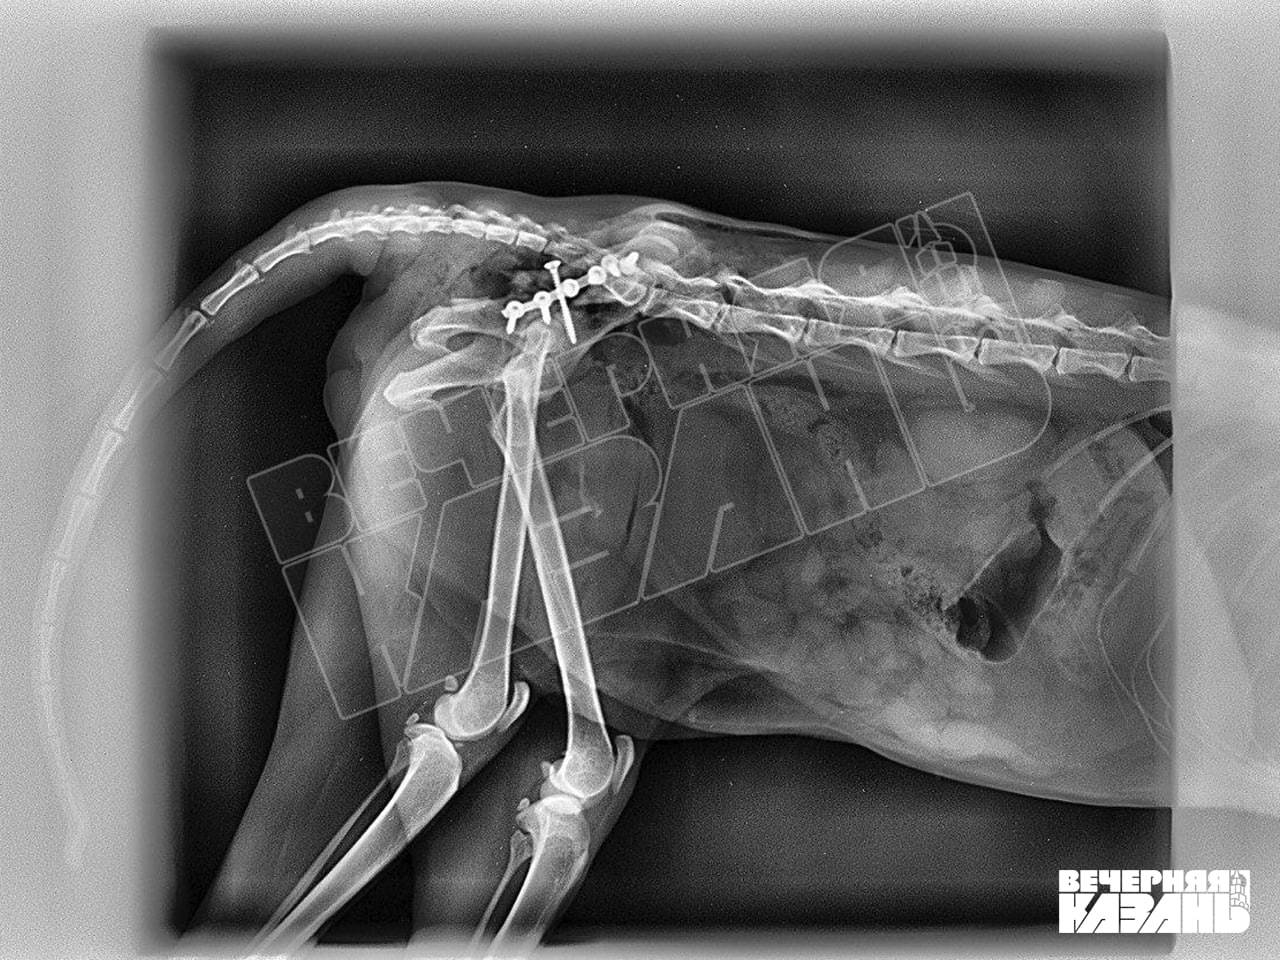

Со слов жителей, бедолага лежала распластанная на асфальте, явно был сломан таз. Марусю, так назвали пострадавшую кошку, привезли в ближайшую ветклинику, где сделали рентген. Оказался двойной перелом. Тогда врач поспешил успокоить, заявив, что операцию делать не нужно и через три недели животное полностью восстановится. Однако на пятый день малышка начала отгрызать лапу, на десятый — все еще не шла на поправку.

В третьей ветклинике врач согласился сделать операцию. Но из-за ринотрахеита (инфекция верхних дыхательных путей у кошек) пришлось отложить ее еще на неделю. Из-за упущенного времени у Маруси было много гематом и кровоизлияния, тем не менее лапу решили не ампутировать. Врач заверил, она может стать опорной, даже если не будет двигаться. Но еще через неделю появилась гангрена, и с лапкой все же пришлось попрощаться. Но даже после этого на том месте продолжали идти гнойные процессы, а где наложили швы, начался некроз.